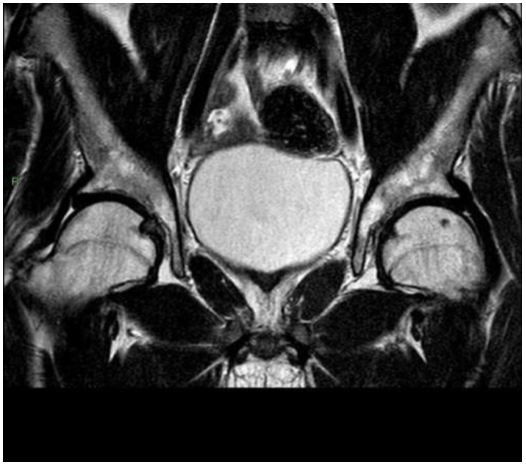

MRI confirmed absent scrotum, testicles, epididymis, prostate gland and seminal vesicles. Furthermore, MRI showed absent corpus spongiosum with normal corpus cavernosum”. Bladder and urethra were normally detectable.

No images compatible with undescended testicles were evident (Figures 1,2 and 3) Subsequently the patient underwent karyotype analysis showing an XY profile.

| Absence of spongy body of urethra, with Absence of corpus spongiosum, with normal corpus

cavernousum. MRI confirmed the absent scrotum sac, testicles, epididymis and related spermatic cords.

Normal representation of bladder- urethral junction. Normal representation of remaining pelvic organs. Figure 1: Sagittal T2-weighted image of pelvic district |

| No images compatible with undescended testicles are evident. Figure 2: Figure 2: Axial T2- weighted image of the pelvic district |

| Prostate gland and seminal vesicles are not evident. Figure 3: Coronal T2 weighted image of pelvic district |